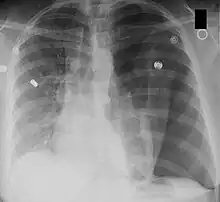

A chest X-ray can rapidly identify a pneumothorax, seen as absence of lung markings. Ultrasound can show the lack of lung sliding. However, imaging should not delay treatment.[8] CT angiography is the standard of diagnosis of pulmonary embolism. Clots appear in the vasculature as filling defects.[18]